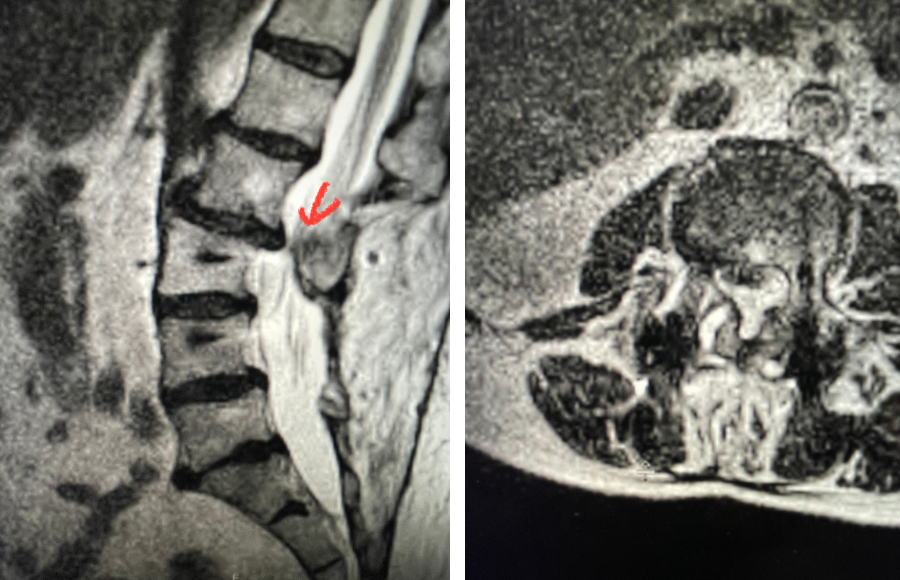

Fig 2: Sagittal T2-weighted MRI of the lumbar spine demonstrating a dysmorphic, trapezoidal-shaped L5 vertebral body (red dot) and a subtle grade 1 spondylolisthesis L5-S1 (blue line).

Another interesting 54-year-old patient presented with low back pain and severe left lower extremity pain over two months. He had a history of falls. The pain in the leg was more bothersome to the patient. The patient had a work-up with an MRI and CT of the lumbar spine. MRI demonstrated a subtle grade 1 spondylolisthesis L5-S1 with a dysmorphic L5 vertebral body (Fig 2). There was a suggestion of a left L5 spondylolysis or defect in the bridge of bone that connects the superior facet process of the segment and the inferior facet process. A CT of the lumbar confirmed this unilateral abnormality which certainly could account for the patient’s left leg pain (Fig 3). This is an unusual finding in that most patients have bilateral pars defects. Patients with L5-S1 often have congenital abnormalities of the lumbosacral junction including weird shaped, elongated or dysplastic facet joints. A subtle L5-S1 spondylolisthesis with an associated smaller and misshapen L5 vertebral body is often associated with L5 spondylolysis. In addition, with a dysmorphic L5 vertebral body, there is secondary disc degeneration at L5-S1 and sometimes at the L4-5 disc with an associated retrolisthesis at L4-5. There is less surface to surface contact of the L4-5 and L5-S1 leading to chronic segmental instability.